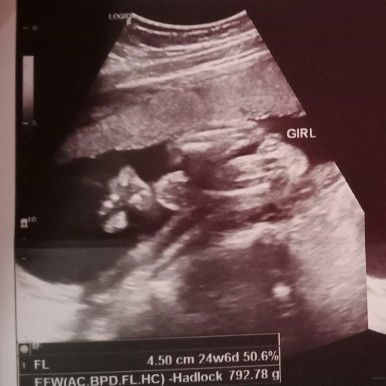

ULTRASOUND RESULT

mga mommy sure po ba na baby girl? and iikot pa po ba siya naka breech po kasi 24weeks po☺️ po#1stimemom #advicepls

Pag nilagyan po ng label, sure na po yan. Iikot pa po yan mii. ☺️